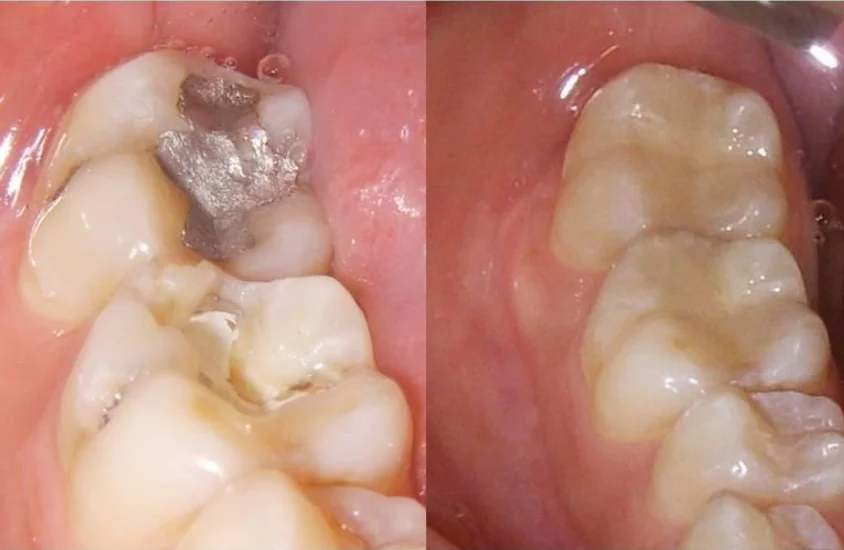

Invisible Restoration

Tooth Color Fillings

At Teeth and Faces Dental clinic, tooth-coloured dental fillings are done to restore teeth that have been damaged by tooth decay or injury.

The cleaning and shaping of teeth prior to the filling is done meticulously. Different types of tooth filling materials are used for different types of cavities in various locations of the teeth, viz. Light cure composite resins, Glass ionomer cements, and laboratory fabricated fillings (inlays/onlays) made of ceramic, composite, or zirconia.

Direct Restoration

Done in the tooth directly. Direct restorations are usually tooth-coloured cavity fillings done in a single appointment for adults as well as children to restore teeth damaged by decay. Light cure composite resins and glass ionomer cement fillings come in this category. We purposely avoid amalgam restorations to keep our clinic and patients mercury-free.

Indirect Restoration

Fabricated outside the mouth in a laboratory to be cemented in the next appointment. Commonly known as Inlays and Onlays, these are specifically used where damage is extensive. They are highly durable restorations made from porcelain, metal, or composite resin. Porcelain is the material of choice because of its immense strength and perfect color match.